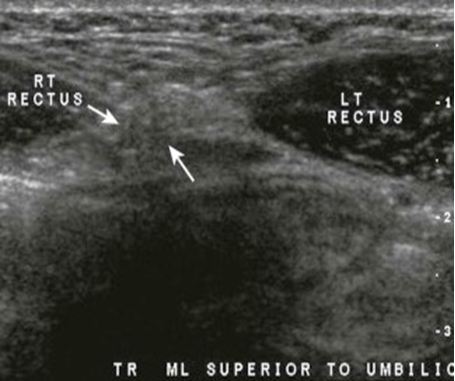

Giant Rectus Sheath Hematoma Causing Abdominal Compartment Syndrome: Review and Management

Ana María Minaya Bravo*, Rita Esther Medina Quintana, Fernado Mendoza Moreno, Julio Cesar Garcia Mahillo